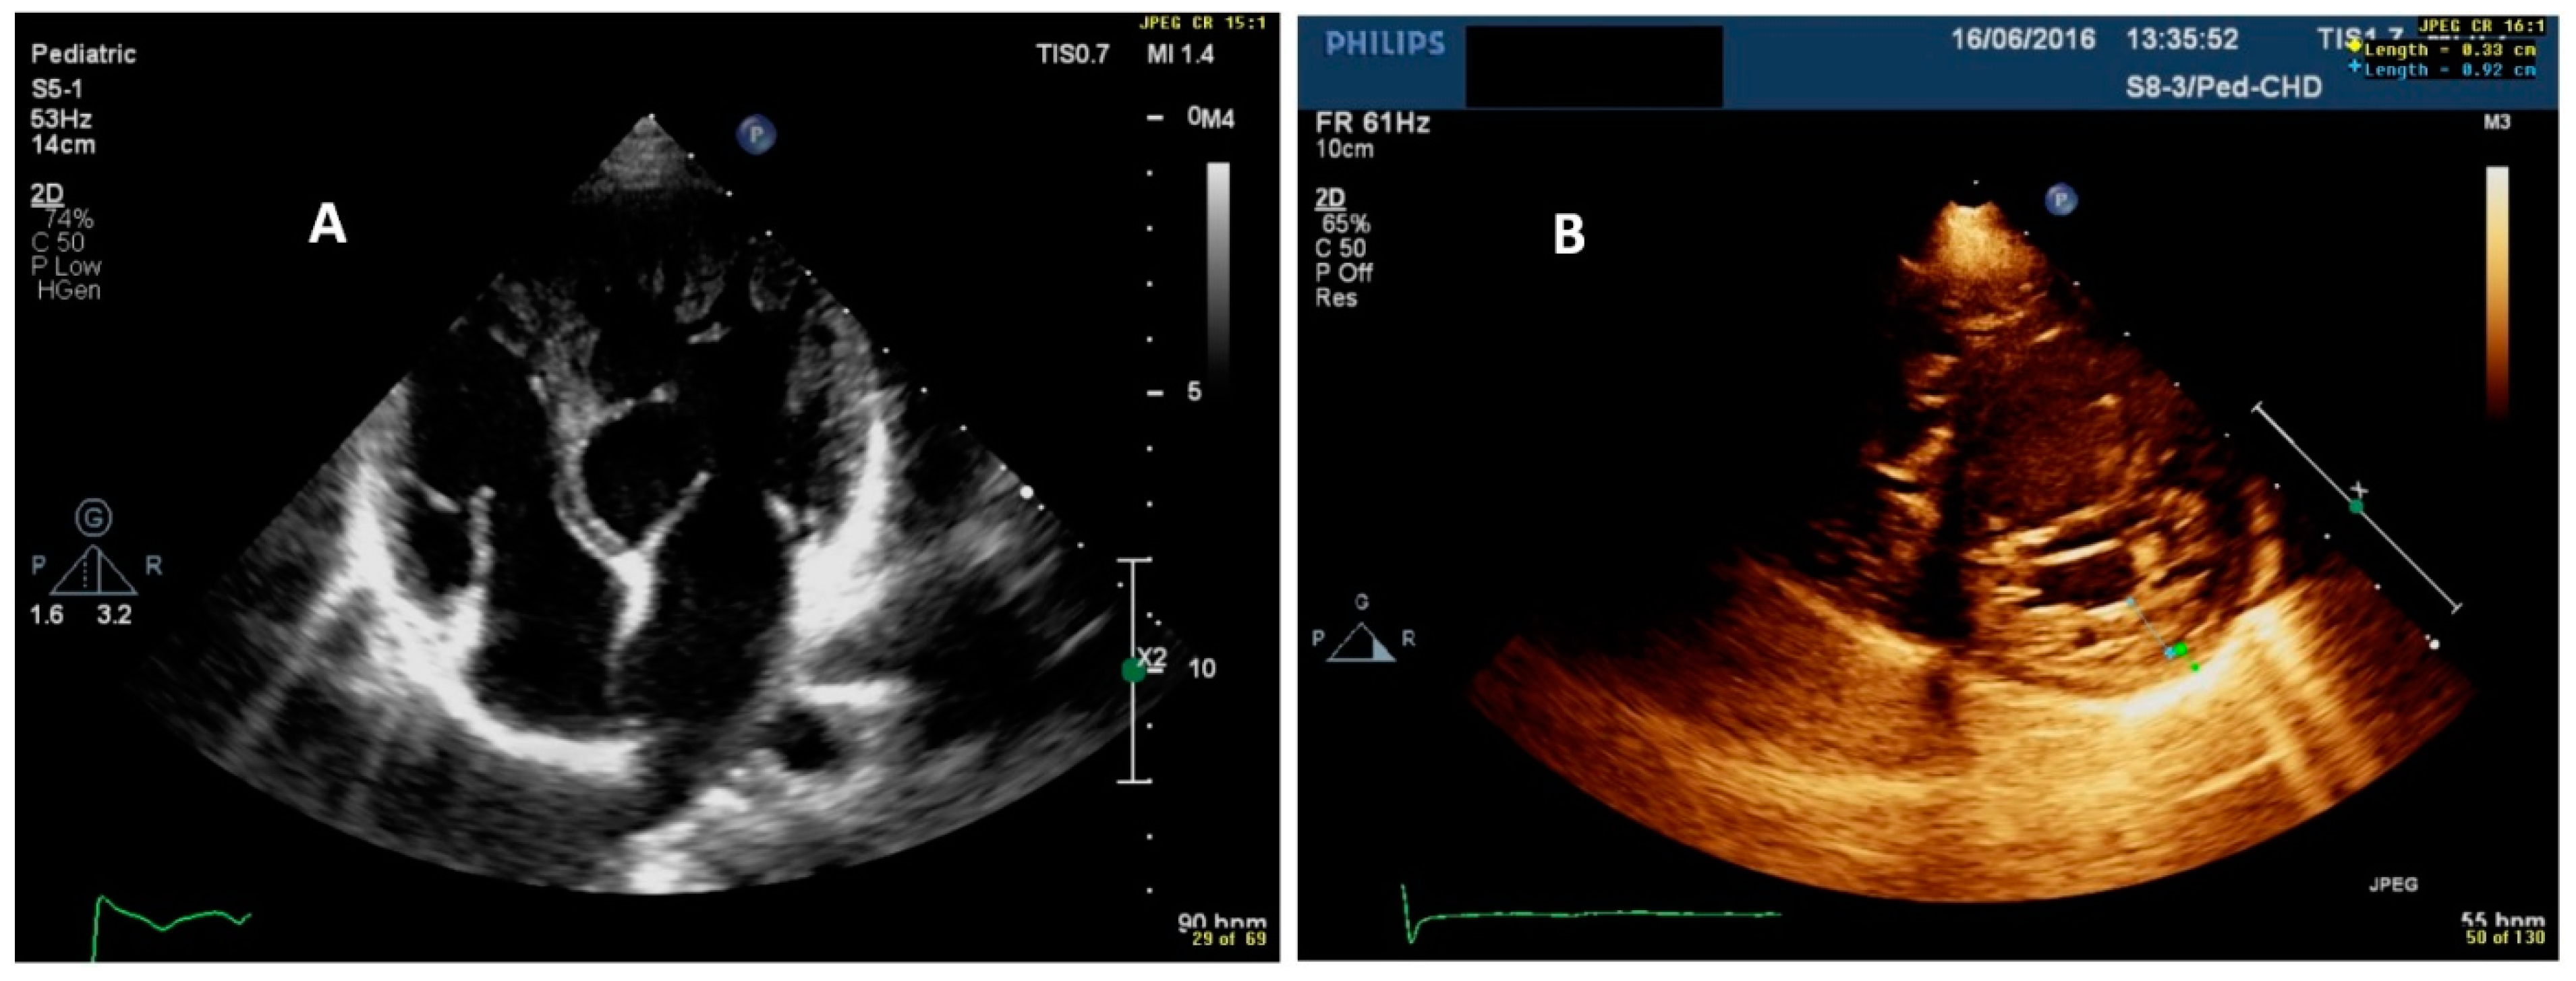

- Echocardiographic examination is the gold standard for the diagnosis of LVNC. However, cardiac CMR is recommended to confirm the diagnosis, especially in uncertain cases.

- Our results indicate that CMR has a good correlation with echocardiography and a high sensitivity and specificity in detecting non-compacted segments.